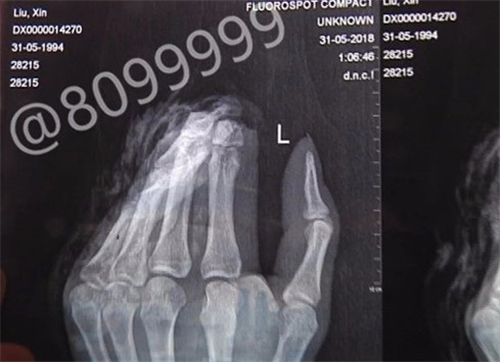

大板桥一小伙两根手指被斩断,在独自辗转求医途中不小心将断指遗失,多个部门和网友全力寻找,很遗憾的是,截至昨晚8点,小刘的两根断指还是没有找到,已错过24小时的最佳手术时间。

时间回到5月30日晚8点,今年24岁,家住大板桥山脚村的小刘,由于妈妈多买了猪脚,怕猪脚摆放变质,准备把猪脚剁成小块放进冰箱冷冻。当剁第二只猪脚时,不小心将自己的食指和中指齐齐剁下,鲜血淋漓。

情况危急,小刘当即用粉白条纹相间的毛巾包起两根断指,前往云桥医院咨询能否治疗。得到否定答案后,他赶往官渡区人民医院。进行简单包扎后,医生让他赶紧去别的医院看看。9时20分左右,小刘打了一辆出租车,赶往延安医院。到达延安医院,医生让他拿出断指时,他才发现断指竟然不见了。因缺少断指,延安医院表示无法无法为小刘做再植手术,只能做残端处理,所以为他推荐到云南骨科医院进行修复重建手术。

抱着一线希望,小刘向云南骨科医院求助,并前往医院就诊。到达医院时,已是31日凌晨1点。云南骨科医院修复重建显微外科中心病区主任曹学新介绍,小刘两根断掉的手指占整根手指约二分之一。如果能在24小时内(昨晚8点前)找到,可通过手术接断指,手指存活可能性较大。“24小时不是绝对的,要看具体情况。如果手指相对完整,这个时间还能延长,但时间越长,成活率越低。”

经过一天的全城搜索,眼看断指找到的机会渺茫,加之时间过去太久,即使找到断指,再接且成活的几率也微乎其微,而小刘的伤口更需要尽快得到处理。考虑再三后,小刘于6月1日上午接受了残端修整手术,手术进行得很顺利,预计一周能出院。

温馨提示:在日常生活中,对于一些利器或机器的使用要格外小心,否则很容易出现手指受伤甚至断指的厄运。如果不慎出现断指意外的时候,正确及时的保存断指十分重要。当伤员要转运到医院进行再植手术时,转运途中要把断指用8至10层无菌纱布或清洁敷料包扎起来,扎紧口后放在冰筒中,在袋外放一些冰块,没有冰块放一些冰糕或雪糕也可以。千万不可将断指放到酒精、甲醛等消毒液中,也不要放到生理盐水中浸泡。一般来说,接回断指的黄金时间是6小时内,越往后成活的几率越低。